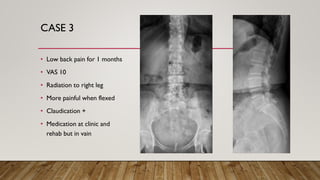

CASE 3

• Low back pain for 1 months

• VAS 10

• Radiation to right leg

• More painful when flexed

• Claudication +

• Medication at clinic and

rehab but in vain